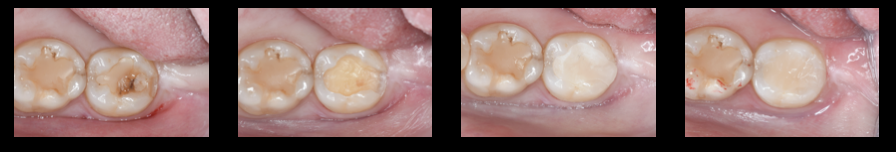

ケース3:コンポジットレジンと歯との間に隙間ができ、虫歯になった歯をセレック(CEREC)を用いて即日オールセラミック修復治療をおこなったケース!!

写真左:術前の写真

写真中左:虫歯除去後の状態(形成後)

写真中右:セラミックブロック(VITA MKⅡ 2M1C)からセラミックインレーを製作。試適時。

写真右:術後の写真